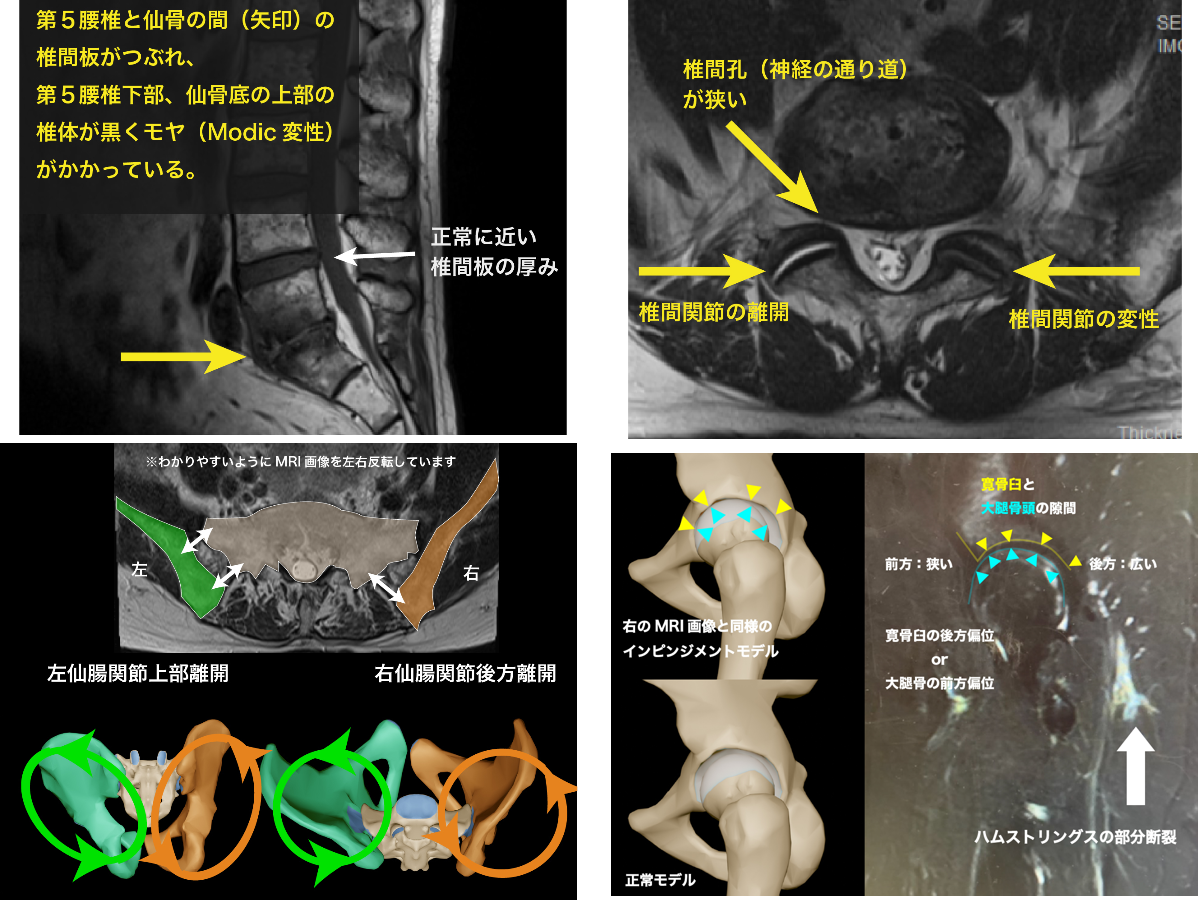

学生時代から学び始めた徒手療法も20年が経ち、開業して15年が経過した今、難治例の仙腸関節の数々を振り返りながら、今なお診ている方の手がかりを探したいと思います。

仙腸関節治療の深化

大腿骨寛骨臼インピンジメントFAIにおいて、勧められる運動療法があります。それが骨盤の後継運動です。今回ご報告するのは、その運動によって仙腸関節の不安定が起こり、難治性の仙腸関節炎になった症例です。

仙腸関節の痛みとFAI(インピンジメント)の関連 鼠蹊部と臀部の痛み